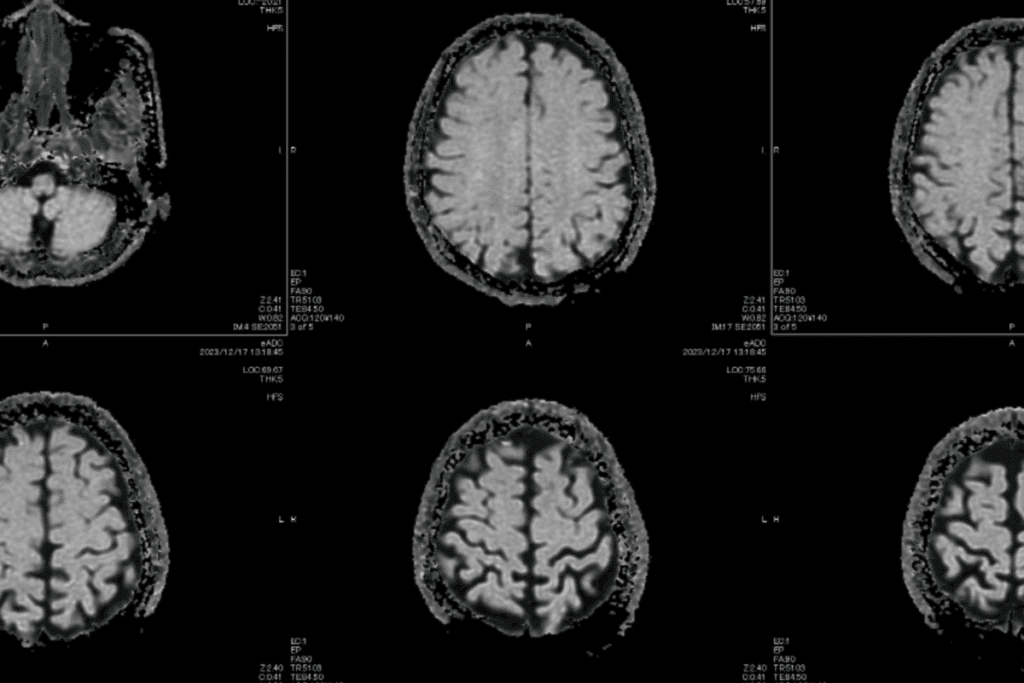

MRI for Soft Tissue Tumor Visualization

Magnetic Resonance Imaging (MRI) is great for seeing soft tissue tumors. It shows details clearly and can tell different tissues apart. MRI helps see how far tumors spread into other areas. This is important for planning surgery.

Key benefits of MRI include:

• High-resolution imaging of soft tissues

• Ability to assess tumor extent and invasion

• Non-invasive and safe for patients